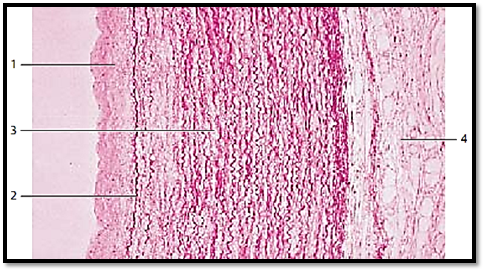

Descending Thoracic Aorta

This cross-section of a thoracic aortic wall exemplifies a typical elastic artery. The tunica intima 1 , followed by the membrana elastica interna 2 adjoin the tunica media . The tunica me dia 3 consists of concentric layers of fenestrated elastic membranes, which are interspersed with myocytes, f ibrocytes, thin collagen fibrils and amorphous substances with a high chondroitin sulfate content. The undulating elastic f ibers stand out in vertical sections. Apart from collagen f ibers, the tunica adventitia 4 also contains elastic fibers, fibrocytes, adipocytes and vasa vasorum .

1 Tunica intima

2 Internal elastic membrane, membrana elastica interna

3 Tunica media

4 Tunica adventitia

Stain: hematoxylin-eosin-resorcin-fuchsin; magnification: × 80